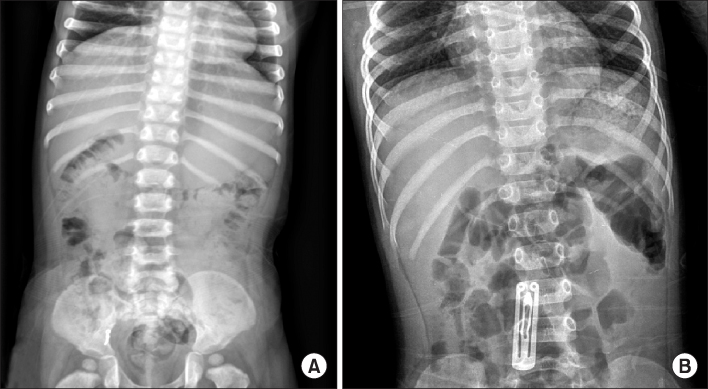

Fig. 2.

(A) Impaction of foreign body in appendix (gold accessory). (B) Impaction of foreign body in small intestine (hair pin).

Fig. 2. (A) Impaction of foreign body in appendix (gold accessory). (B) Impaction of foreign body in small intestine (hair pin).